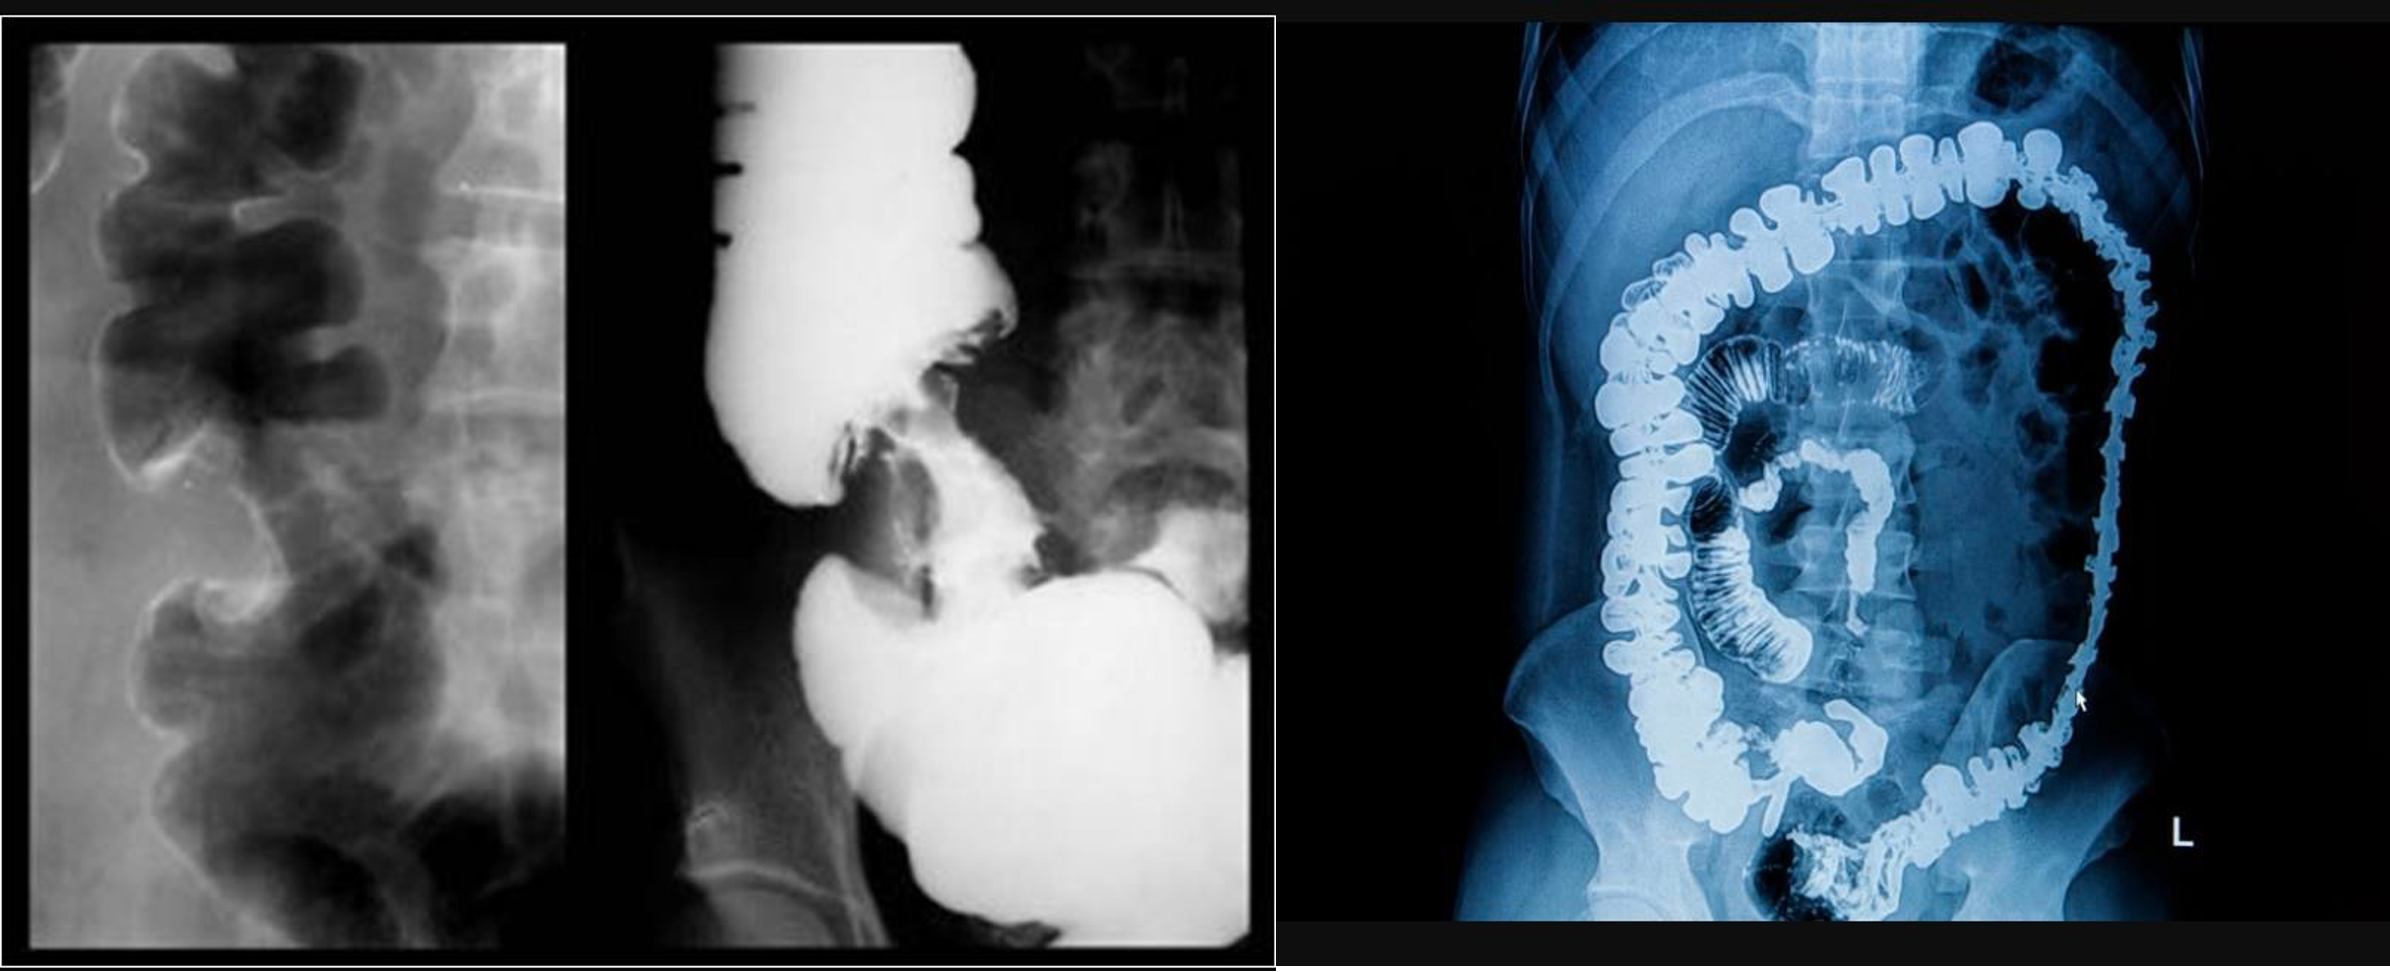

Abdomen Imaging

normal abdominal x-ray - normal gas pattern - lower pole kidney - gastric bubble is found - comment on bone

Free air under diaphragm - most commonly due duodenal perforation - (diff; perforated viscus, peptic ulcer, duodenal, penetrating truama, post surgical 8 days likely to disappear)

- free air

- erect - air fluid levels - should be not more than three - >5 significant 11 found -

- no free air under diaphgram - 8 fluid level, (evidence of bowel obstruction) (adhesion, hernia, IBD; Crohn, cancer, inturcucception, gallstones)

9 air fluids in large bowel - mucosal folds are not completed - highly suggestive of bowel obstruction

- dilated large bowel - mucosal folds are not complete - (diff; cancer, divertuclitis, volvolus, toxic megacolon?)

- if both small and large most likely nonmechanical paralytical illeus

2) Dilated bowel (diff; cancer colon) -

closed loop obstruction from both sides result large bowel most dangerous left side most common cancers

- coffe bean - omega sign - volvulus twisting around its axis - it is closed loop obstruction very dangerous - (treat clonoscopy decompression)

- volvulus

- abdominal x-ray - Dilated colon (diff - cancer colon, ulcerative colittis)